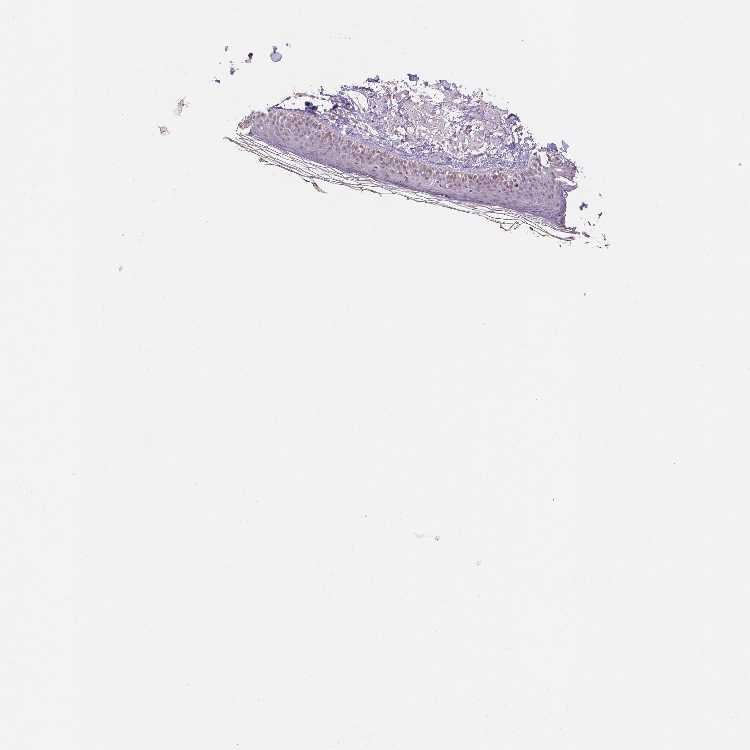

SKIN 2 - Antibody stainingi

Antibody staining in the annotated cell types in the current human tissue is reported as not detected, low, medium, or high, based on conventional immunohistochemistry profiling in selected tissues. This score is based on the combination of the staining intensity and fraction of stained cells.

Each image is clickable and will lead to virtual microscopy that enables deeper exploration of all samples and also displays staining intensity scores, fraction scores and subcellular localization as well as patient and tissue information for each sample.

Antibody HPA037366Antibody HPA050388Antibody CAB032654

Cells in basal layer Medium--

Cells in corneal layer Not detected--

Cells in granular layer Low--

Cells in spinous layer Medium--

Endothelial cells Low--

Epidermal cells -LowLow

Extracellular matrix Not detected--

Fibrohistiocytic cells Not detected--

Langerhans cells Medium--

Lymphocytes Low--

Melanocytes Not detected--

Vascular mural cells Not detected--